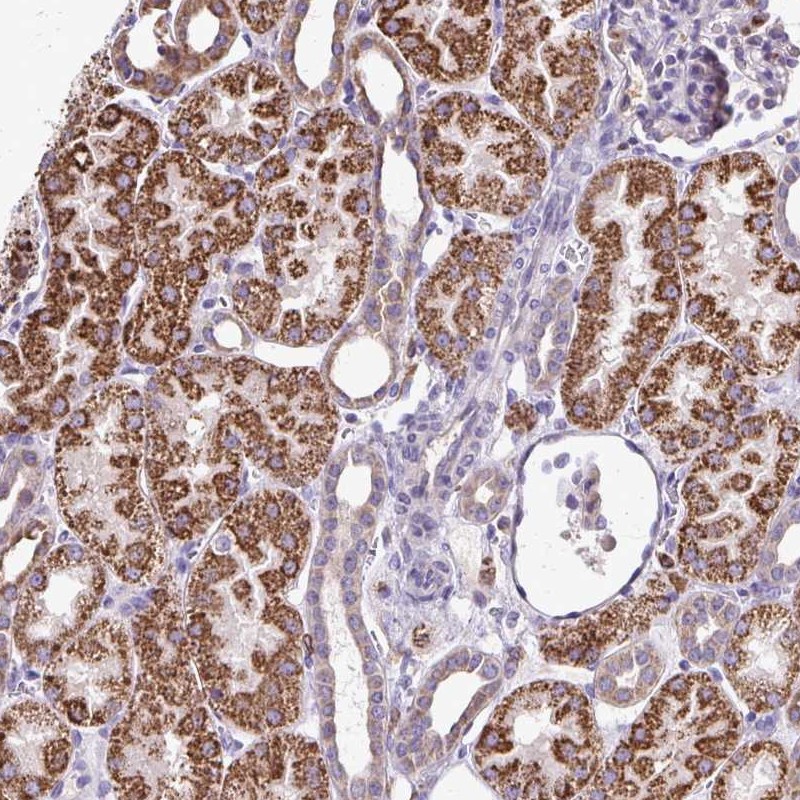

Immunohistochemical staining of human kidney shows strong cytoplasmic positivity in cells in tubules.